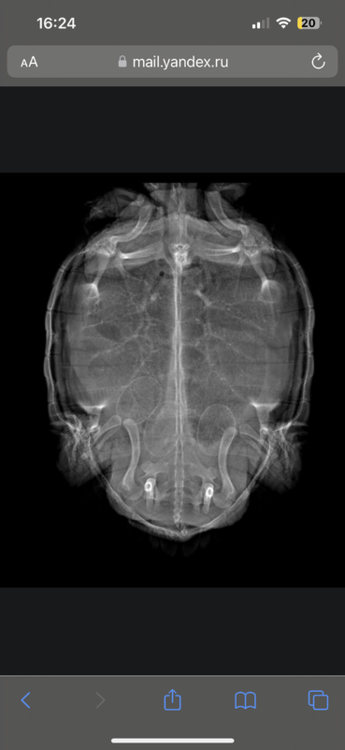

ЕленаЧ Ваше имя: Елена Локация: Москва Опубликовано: 17 апреля 2023 Автор Опубликовано: 17 апреля 2023 У нас 2 кладка яиц намечается, в этот раз 10 и больше размером, герпетолог сказал также схема, борглюконат кальция 0,9 мл 5-7 дней, если сама не отдаст еще по 2 мл окситоцин через каждые 12 ч но не более 3 раз … кушает, какает, но днем спит весь день на мостике, это прям смущает, в воде попу не может поднять чтобы плавать, либо по дну ходит либо вдоль аквариума на задних лапах

ЕленаЧ Ваше имя: Елена Локация: Москва Опубликовано: 21 апреля 2023 Автор Опубликовано: 21 апреля 2023 Откололи по 0,9 мл 5 дней кальция и черепаха даже не планирует рожать, ест как не в себя, плавает и греется, назначили 2 мл разово окситоцин через каждые 12 ч но не более 3 раз, если не поможет то оперировать ? не знаю что надо делать чтобы сама делала, слежу за такой же черепашкой Тузей так там также ситуация, 2 кладка за весну , перестала капать, начала есть и какая-то как до беременности и тоже не хочет сама отдать яйца , в этом году что-то аномальное столь?

Алексей Alex-Raduga Ваше имя: Алексей Локация: Россия, МО, Серпуховский район Опубликовано: 22 апреля 2023 Опубликовано: 22 апреля 2023 @ЕленаЧ по рентгену не сказали, все нормально ? Но если назначили окситоцин и другое не помогло - придется делать.